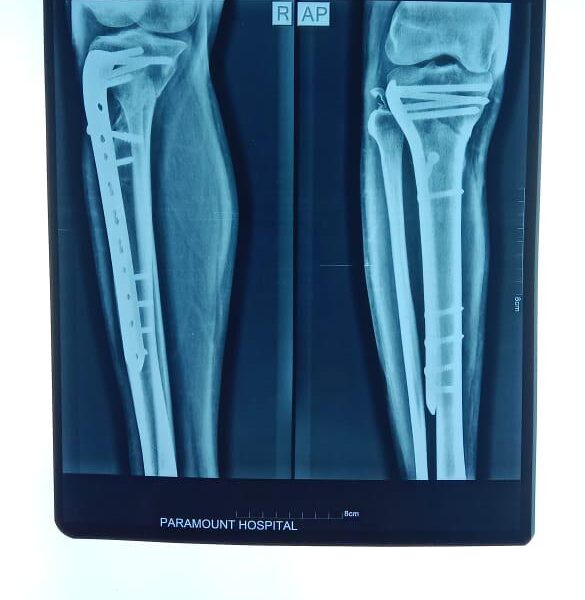

Moments That Mark Meaningful Recovery

Witness real patient transformations at The Ortho Clinic through images that reflect successful treatments and restored mobility.